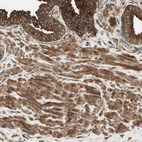

Immunohistochemical staining of human placenta shows strong cytoplasmic and membranous positivity in trophoblastic cells.